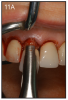

An implant most closely replicates the feel of a natural tooth. Once it is osseointegrated, many patients cannot differentiate an implant from a natural tooth. Furthermore, dental implants do not decay or need a root canal. Even though the cost is slightly more than a bridge, it is a great investment for the future, as implants usually last longer than a bridge. A 10-year report on posterior single implants shows a success rate of 97%.29 Once an implant is placed, an integration/healing time of approximately 4 months is necessary before final crown is placed. A temporary crown can be placed the same day the implant is placed. (Figures 11A-E)

Figure 11A – Extraction of anterior tooth (#8) without detaching the gingiva

Figure 11A

Figure 11B – Extracted tooth with the root canal material (gutta percha) extending from the apex

Figure 11B

Figure 11C – A zircon (white) abutment was attached immediately following the extraction and implant placement

Figure 11C

Figure 11D – Immediate placement of temporary crown over the abutment; laser crown lengthening was performed on the adjacent teeth to improve gingival symmetry

Figure 11D

Figure 11E – Four months post surgery with temporary crown over

implant at #8

Figure 11E